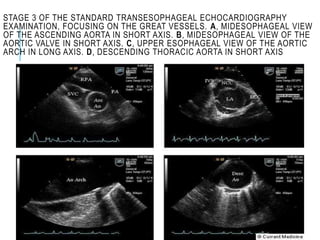

STAGE 3 OF THE STANDARD TRANSESOPHAGEAL ECHOCARDIOGRAPHY

EXAMINATION, FOCUSING ON THE GREAT VESSELS. A, MIDESOPHAGEAL VIEW

OF THE ASCENDING AORTA IN SHORT AXIS. B, MIDESOPHAGEAL VIEW OF THE

AORTIC VALVE IN SHORT AXIS. C, UPPER ESOPHAGEAL VIEW OF THE AORTIC

ARCH IN LONG AXIS. D, DESCENDING THORACIC AORTA IN SHORT AXIS